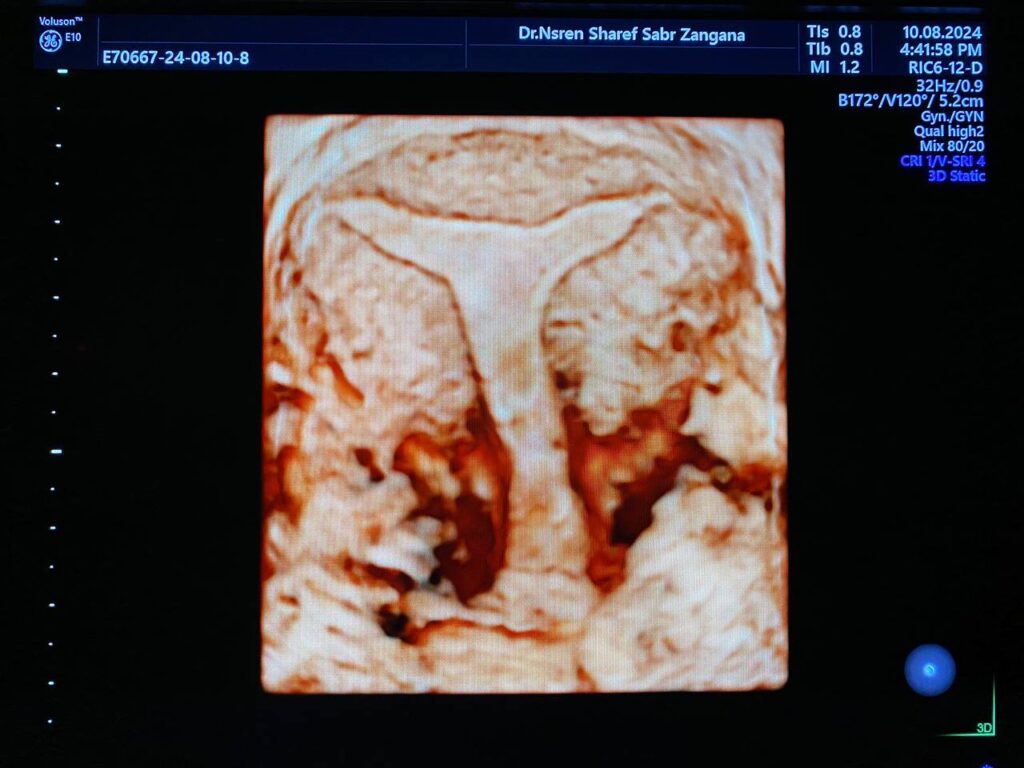

Arcuate fundal surface with fundal depression about 1.5mm, both lateral wall are medially displaced ,narrow cavity, T shape cavity ?? Surface rendering & Omni view